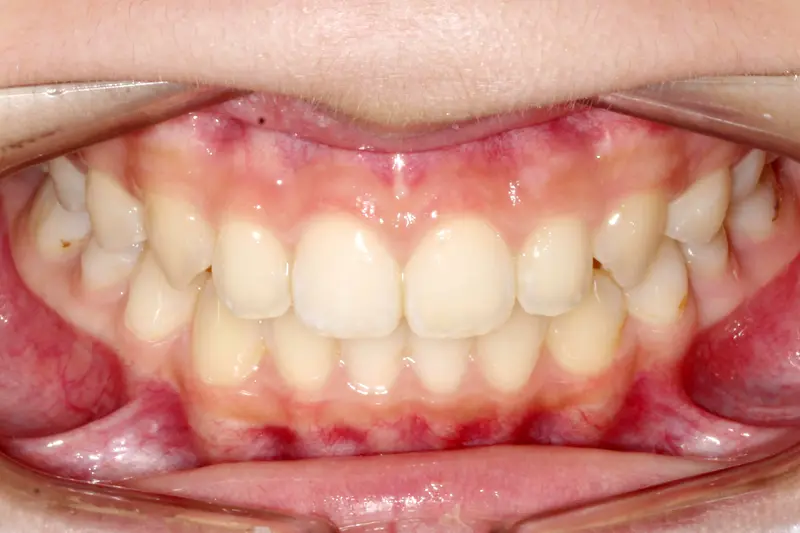

After treatment: The Expansion Phase

After

Before treatment: The Expansion Phase

Before

Severe crowding with blocked-out permanent teeth. The jaw size was insufficient to accommodate the erupting adult teeth, leading to significant rotation and displacement.

By intervening early, we utilized rapid palatal expansion to develop the arch width. This created the necessary space for the permanent teeth to erupt naturally, avoiding the need for future extractions.